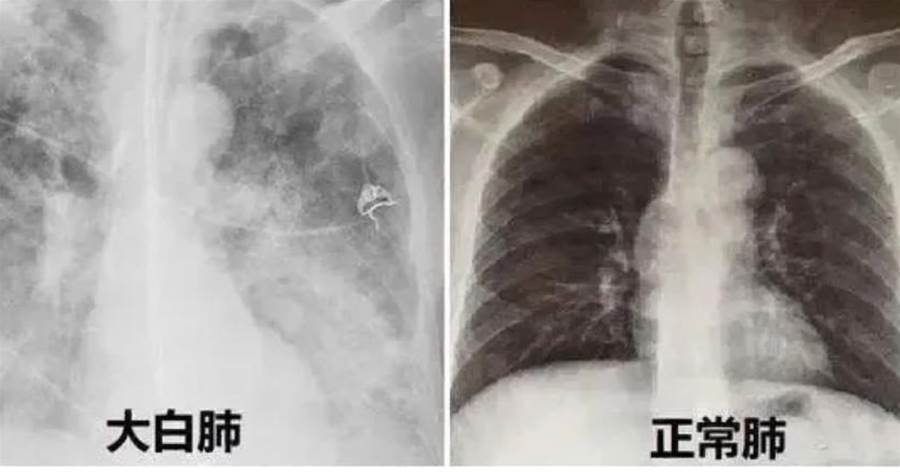

「白肺」并非一個專業的醫學名詞或獨立的疾病,而是一個形象化的描述。它源于醫學影像學,特指肺部在X光或CT掃描中顯示為大面積白色的一種現象。

具體來說,當這種白色覆蓋至少一半的肺(也有說法認為白色面積達到70%~80%時),就被稱為「白肺」。這種現象通常意味著肺部已經遭受了嚴重的損傷,影響了氣體的正常交換功能,進而可能導致呼吸困難、缺氧等嚴重后果。